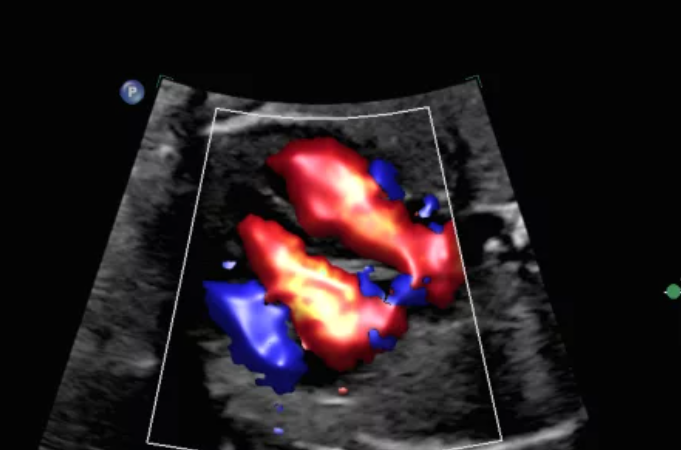

ЦДК перфузии яичника с Flow Viewer с датчиком C10-3v

MFI яичника, Flow Viewer

Кровоток в яичнике с MFI и датчиком C10-3v